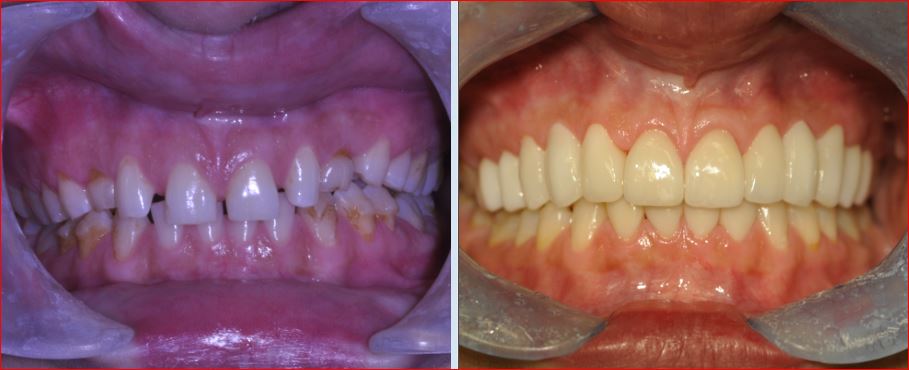

COMPLETE CONSERVATIVE SMILE MAKEOVER

This beautiful young lady came to our cosmetic dental practice with the desire to get a better smile.

Her previous Invisalign orthodontic treatment done by another dentist had failed to deliver any result due to the poor treatment planning. After completing a detailed smile analysis, Dr. Andrews recommended a new physiological (Neuromuscular) bite in order to:

- improve the lower face proportions

- to balance and relax the muscles

- to increase the lengths of the teeth

Once her new bite was established, the restorative phase of the cosmetic dental treatment had followed with 12 upper and 5 lower teeth receiving metal-free, all-ceramic restorations equilibrated into perfect balance with her muscles and joints (TMJ). Cavities on the remaining teeth were treated with conservative bio-mimetic, mercury-free composite white fillings.